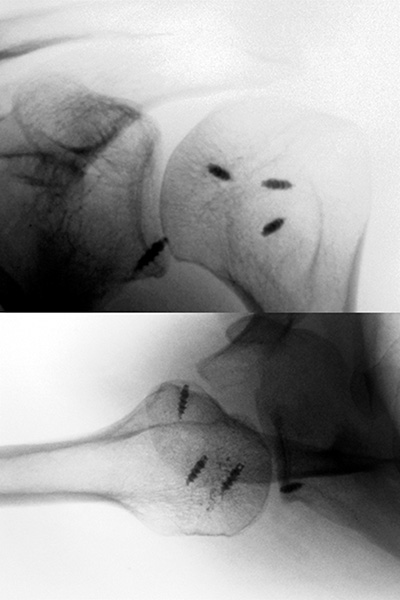

Rx. Antero-Posterior: típica imagen de luxación posterior (Fig. 1).

T.A.C.:Luxación posterior con defecto óseo anterior (Fig. 2). Ante dicho hallazgo se realizó reducción incruenta bajo neurolepto analgesia, siendo esta satisfactoria, y se inmovilizó con un cabestrillo. Es controlado en consultorio externo de la especialidad a los 10 días de evolución. Se completaron los estudios.

Estudios Complementarios Post reducción:Rx. A.P., Control de reducción (Figs. 3), TAC simple y con Reconstrucción 3D: se evidencia fractura osteocondral de la cabeza humeral en sector anteromedial (Fig. 4), RMN: se evidencia avulsión de la capsula, el labrum postero-inferior y el fragmento libre osteocondral (Fig. 5). Se indicó tratamiento quirúrgico, el cual fue realizado con 3 semanas de evolución.

Figura 1: Rx. A.P. Hombro Izquierdo: Imagen en luna llena características de luxación posterior.

Figura 2: T.A.C. Simple: Luxación posterior gleno-humeral con defecto óseo en región antero-medial.

Figura 3: Rx. AP Post-Reducción: Imagen de discontinuidad de la interlínea articular, por fragmento óseo.

Figura 4: A) T.A.C. simple: Cuantificación u locación del defecto óseo en la región antero-medial de la superficie articular humeral. Fragmento libre en cavidad. B)3-D: Valoración y cuantificación del fragmento osteo-condral y su relación al momento del estudio.